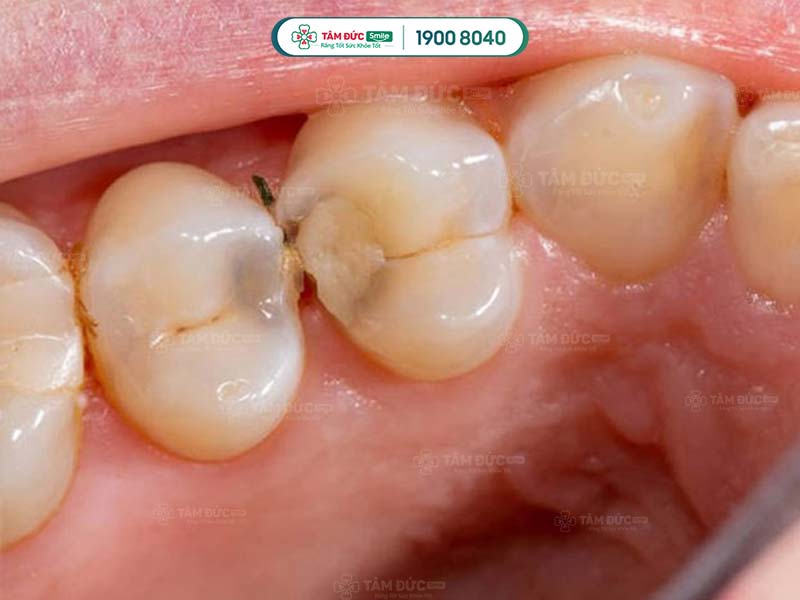

1.1. Kẽ răng hàm bị đen do sâu răng

Sâu răng là nguyên nhân chính làm kẽ răng hàm bị đen hoặc làm cho răng bị đổi màu. Sâu răng do vi khuẩn tấn công, phá hủy men răng và ngà răng. Chúng tiết ra axit làm mòn mô cứng, tạo ra các lỗ nhỏ trên răng. Theo thời gian, các lỗ nhỏ này dần phát triển thành lỗ đen mà Quý khách có thể nhìn thấy bằng mắt thường.

Trong đó, sâu răng chủ yếu xảy ra ở rìa răng và kẽ hở giữa các răng. Đây cũng là nguyên nhân phổ biến làm kẽ răng bị đen, gây mất thẩm mỹ.